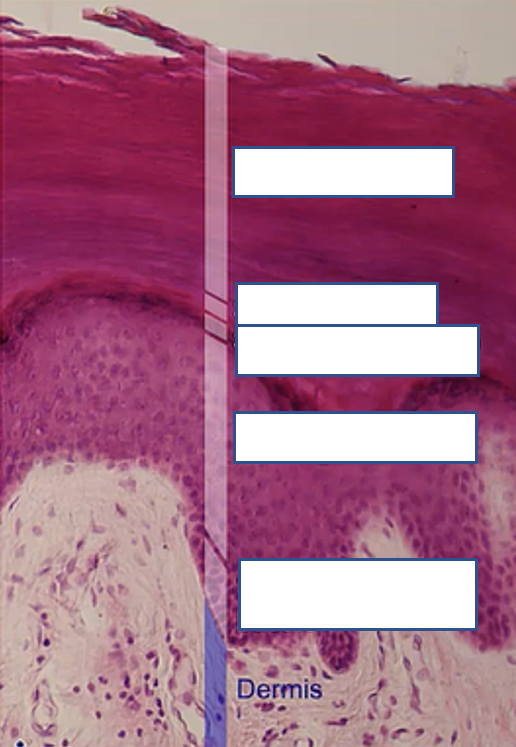

what are the numbered regions of the epidermis

1: stratum basale

2. stratum spinale

3. stratum granulosum

4. stratum lucidum

5. stratum corneum